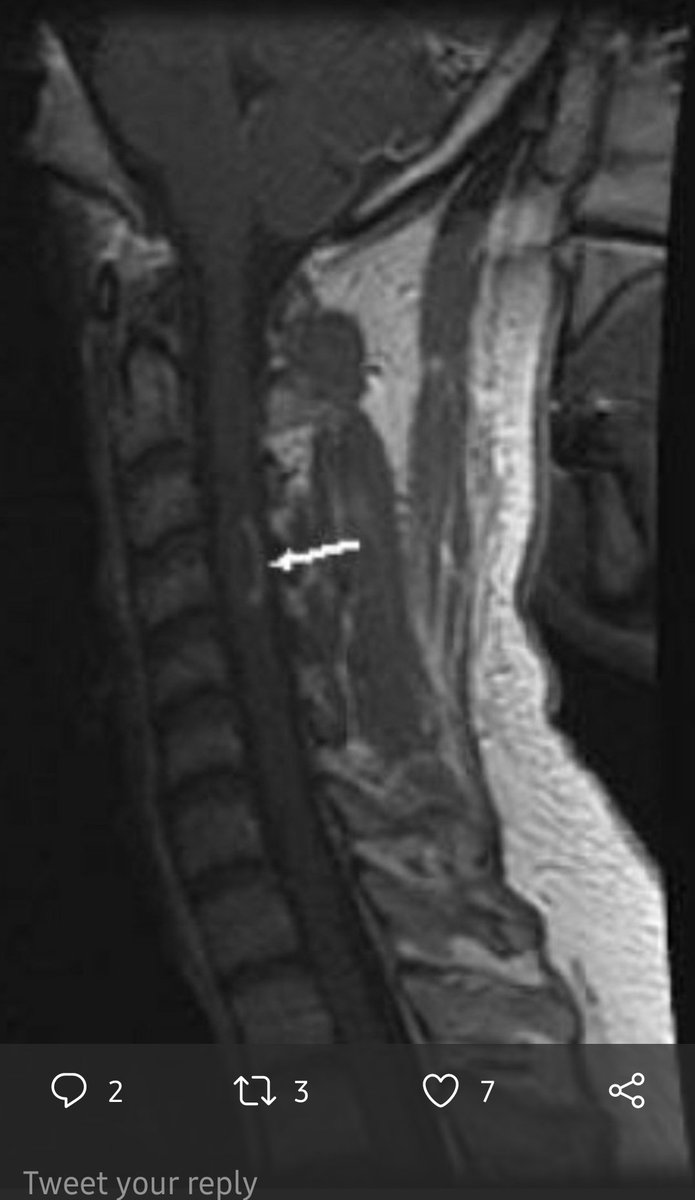

♦️ورنين مغناطيسي للمخ والحبل الشوكي